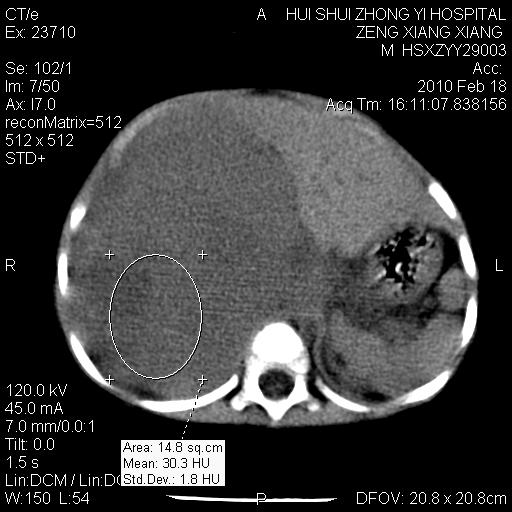

标题: PED3106:男,2岁,腹胀1月。 [打印本页]

标题: PED3106:男,2岁,腹胀1月。

定位腹膜后,肾上腺来源;

定性:恶性神经源性,肾上腺神经节母细胞瘤可能性大。

鉴别:肝母、肾母、肝脏中胚层错构瘤。

依据:年龄、有钙化,肾脏及肝脏受压移位。